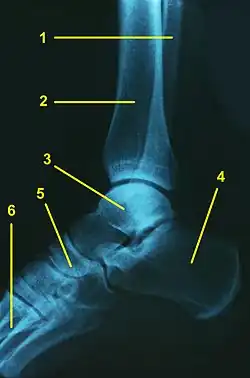

Legende:

1 – Wadenbein (Fibula)

2 – Schienbein (Tibia)

3 – Sprungbein (Talus)

4 – Fersenbein (Calcaneus)

5 – Kahnbein (Os naviculare)

6 – Mittelfußknochen (Os metatarsi)